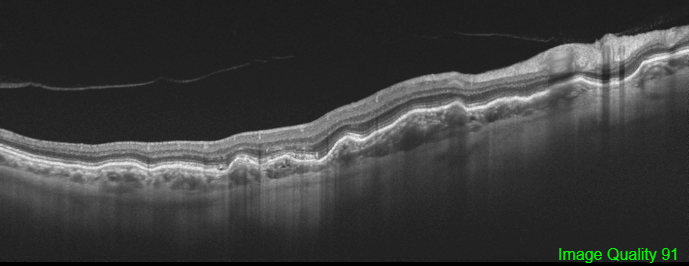

Optical coherence tomography shows the characteristics undulations of the RPE consistent with choroidal folds with a nearly flat retinal surface and a variable retinal thickness, increasing in correspondence to the valleys and reducing in the crests